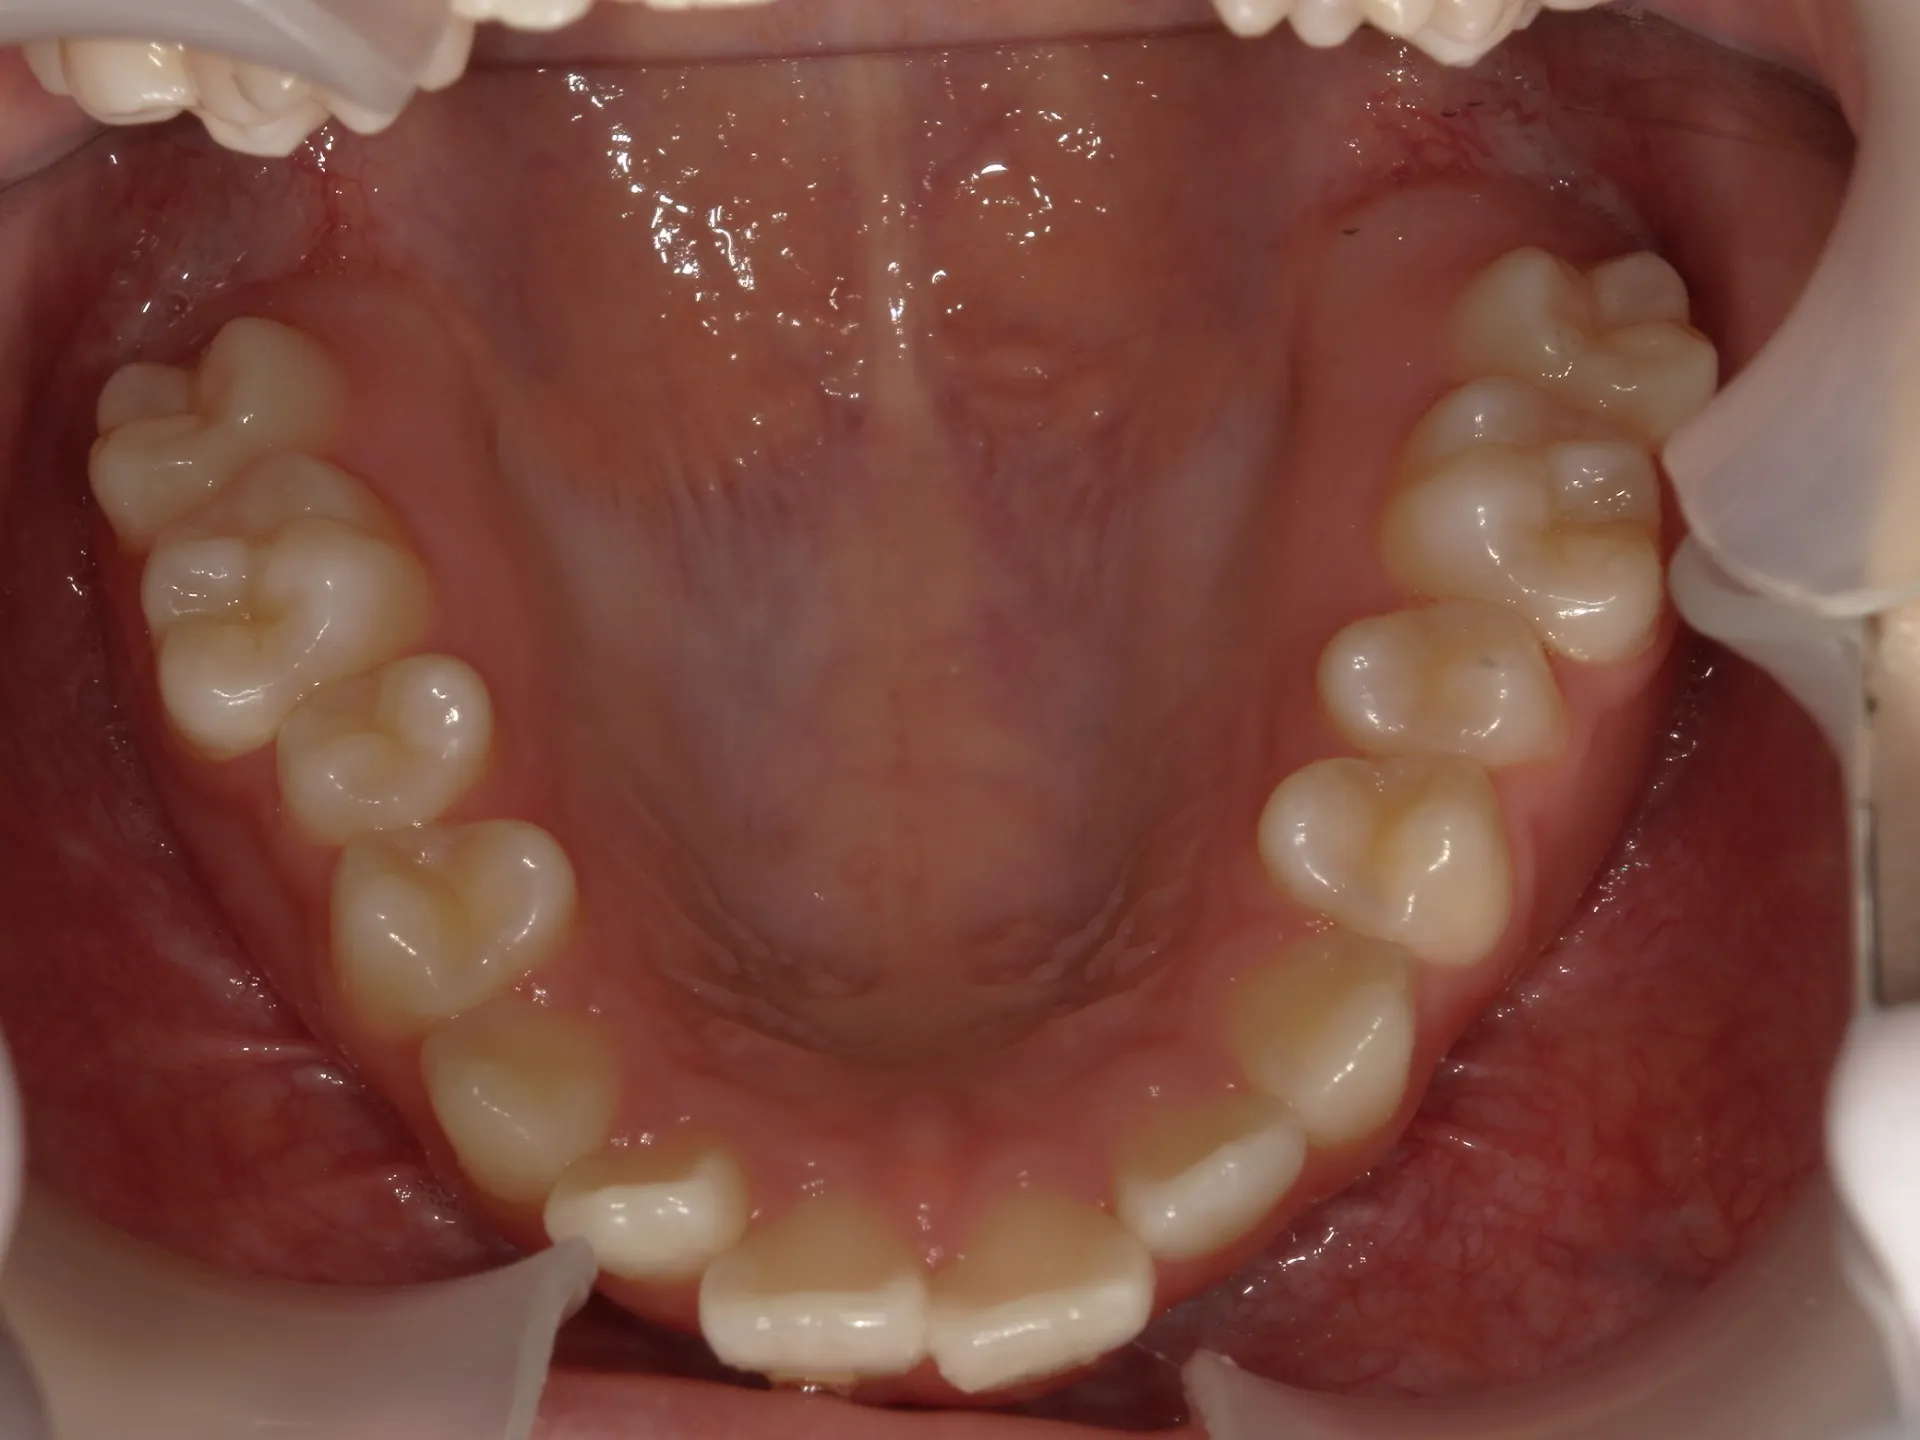

開咬治療前

まず開咬とは、文字通り開いている咬み合わせのことをさします。

分かりにくい方もいるかもしれませんのでもう少し説明すると、今回お見せしている写真では前歯部開咬と呼ばれる開咬です。

臼歯(奥歯)は噛んでいるのに前歯が咬みあわないで開いているという状態のことを前歯部開咬と言います。

さて、治療前の正面観は先ほど述べた通り、前歯部開咬で奥にある舌が見えているのが分かります。